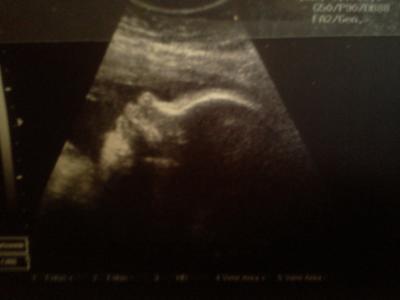

FA Termin mit CTG Super gewesen.

Bis auf mein Eisenwert da muss ich ab morgen Tabletten nehmen aber Bildchen gab es wie immer mit ^^ ICH LIEBE DIESES KIND!! Beim CTG hat er voll gepennt ^^

Bild zu FA Termin mit CTG Super gewesen. - Forum für Juli - Mamis